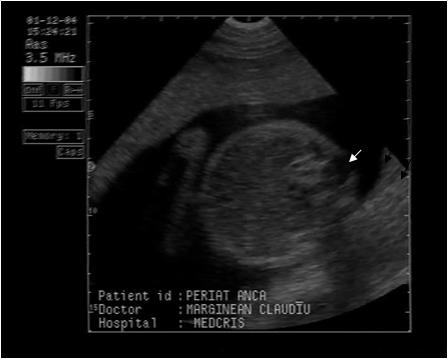

Fig . nr. 248. Chist de plex choroid , unilateral, la o sarcina de 17 sapt.

Fig. nr. 249. Hidrocefalie interna unilaterala aparuta la 28 sapt si cu evolutie rapida, postpartum se confirma suspiciunea de diagnostic: hemoragie cerebrala